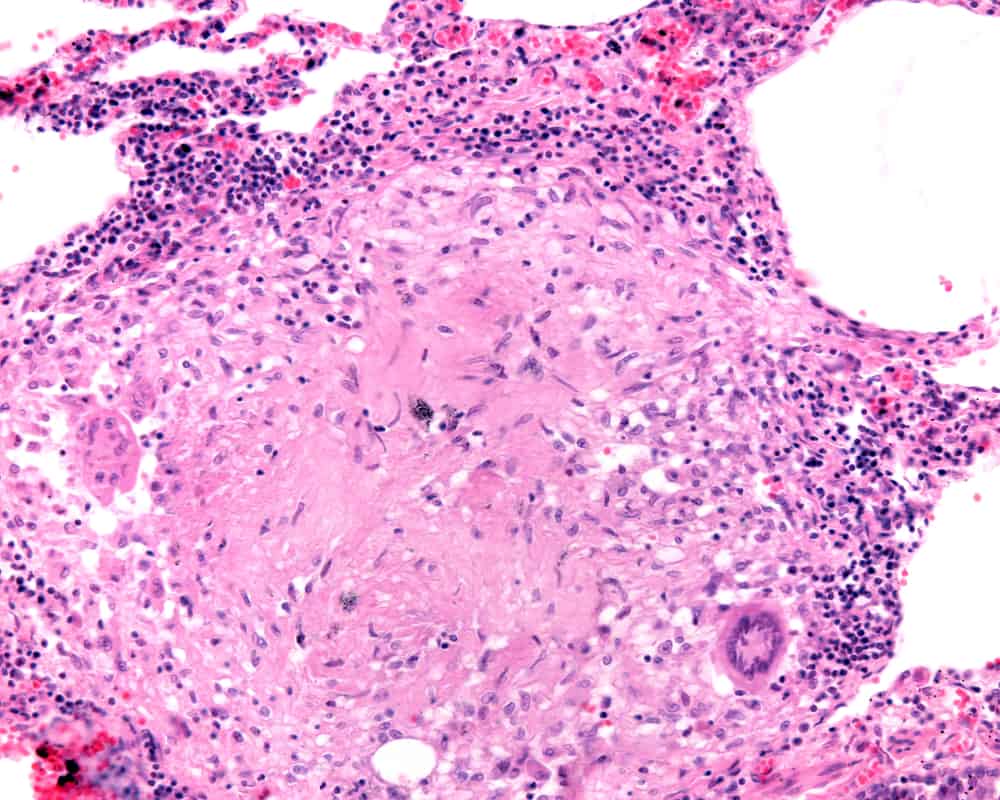

What are granuloma in lungs? Granulomas are small cells that are clumped together when lung tissues become inflamed. Actually, it is the body’s defense mechanism when the immune system detects foreign substances invading the body.

Granulomas are more likely to occur in the lungs than in any other organ in the body. And they have the tendency to calcify over time due to the calcium that forms during the healing process.

Granulomas in lungs can either be cancerous or noncancerous. However, please note that people who are diagnosed with this finding mostly have noncancerous or benign granulomas.